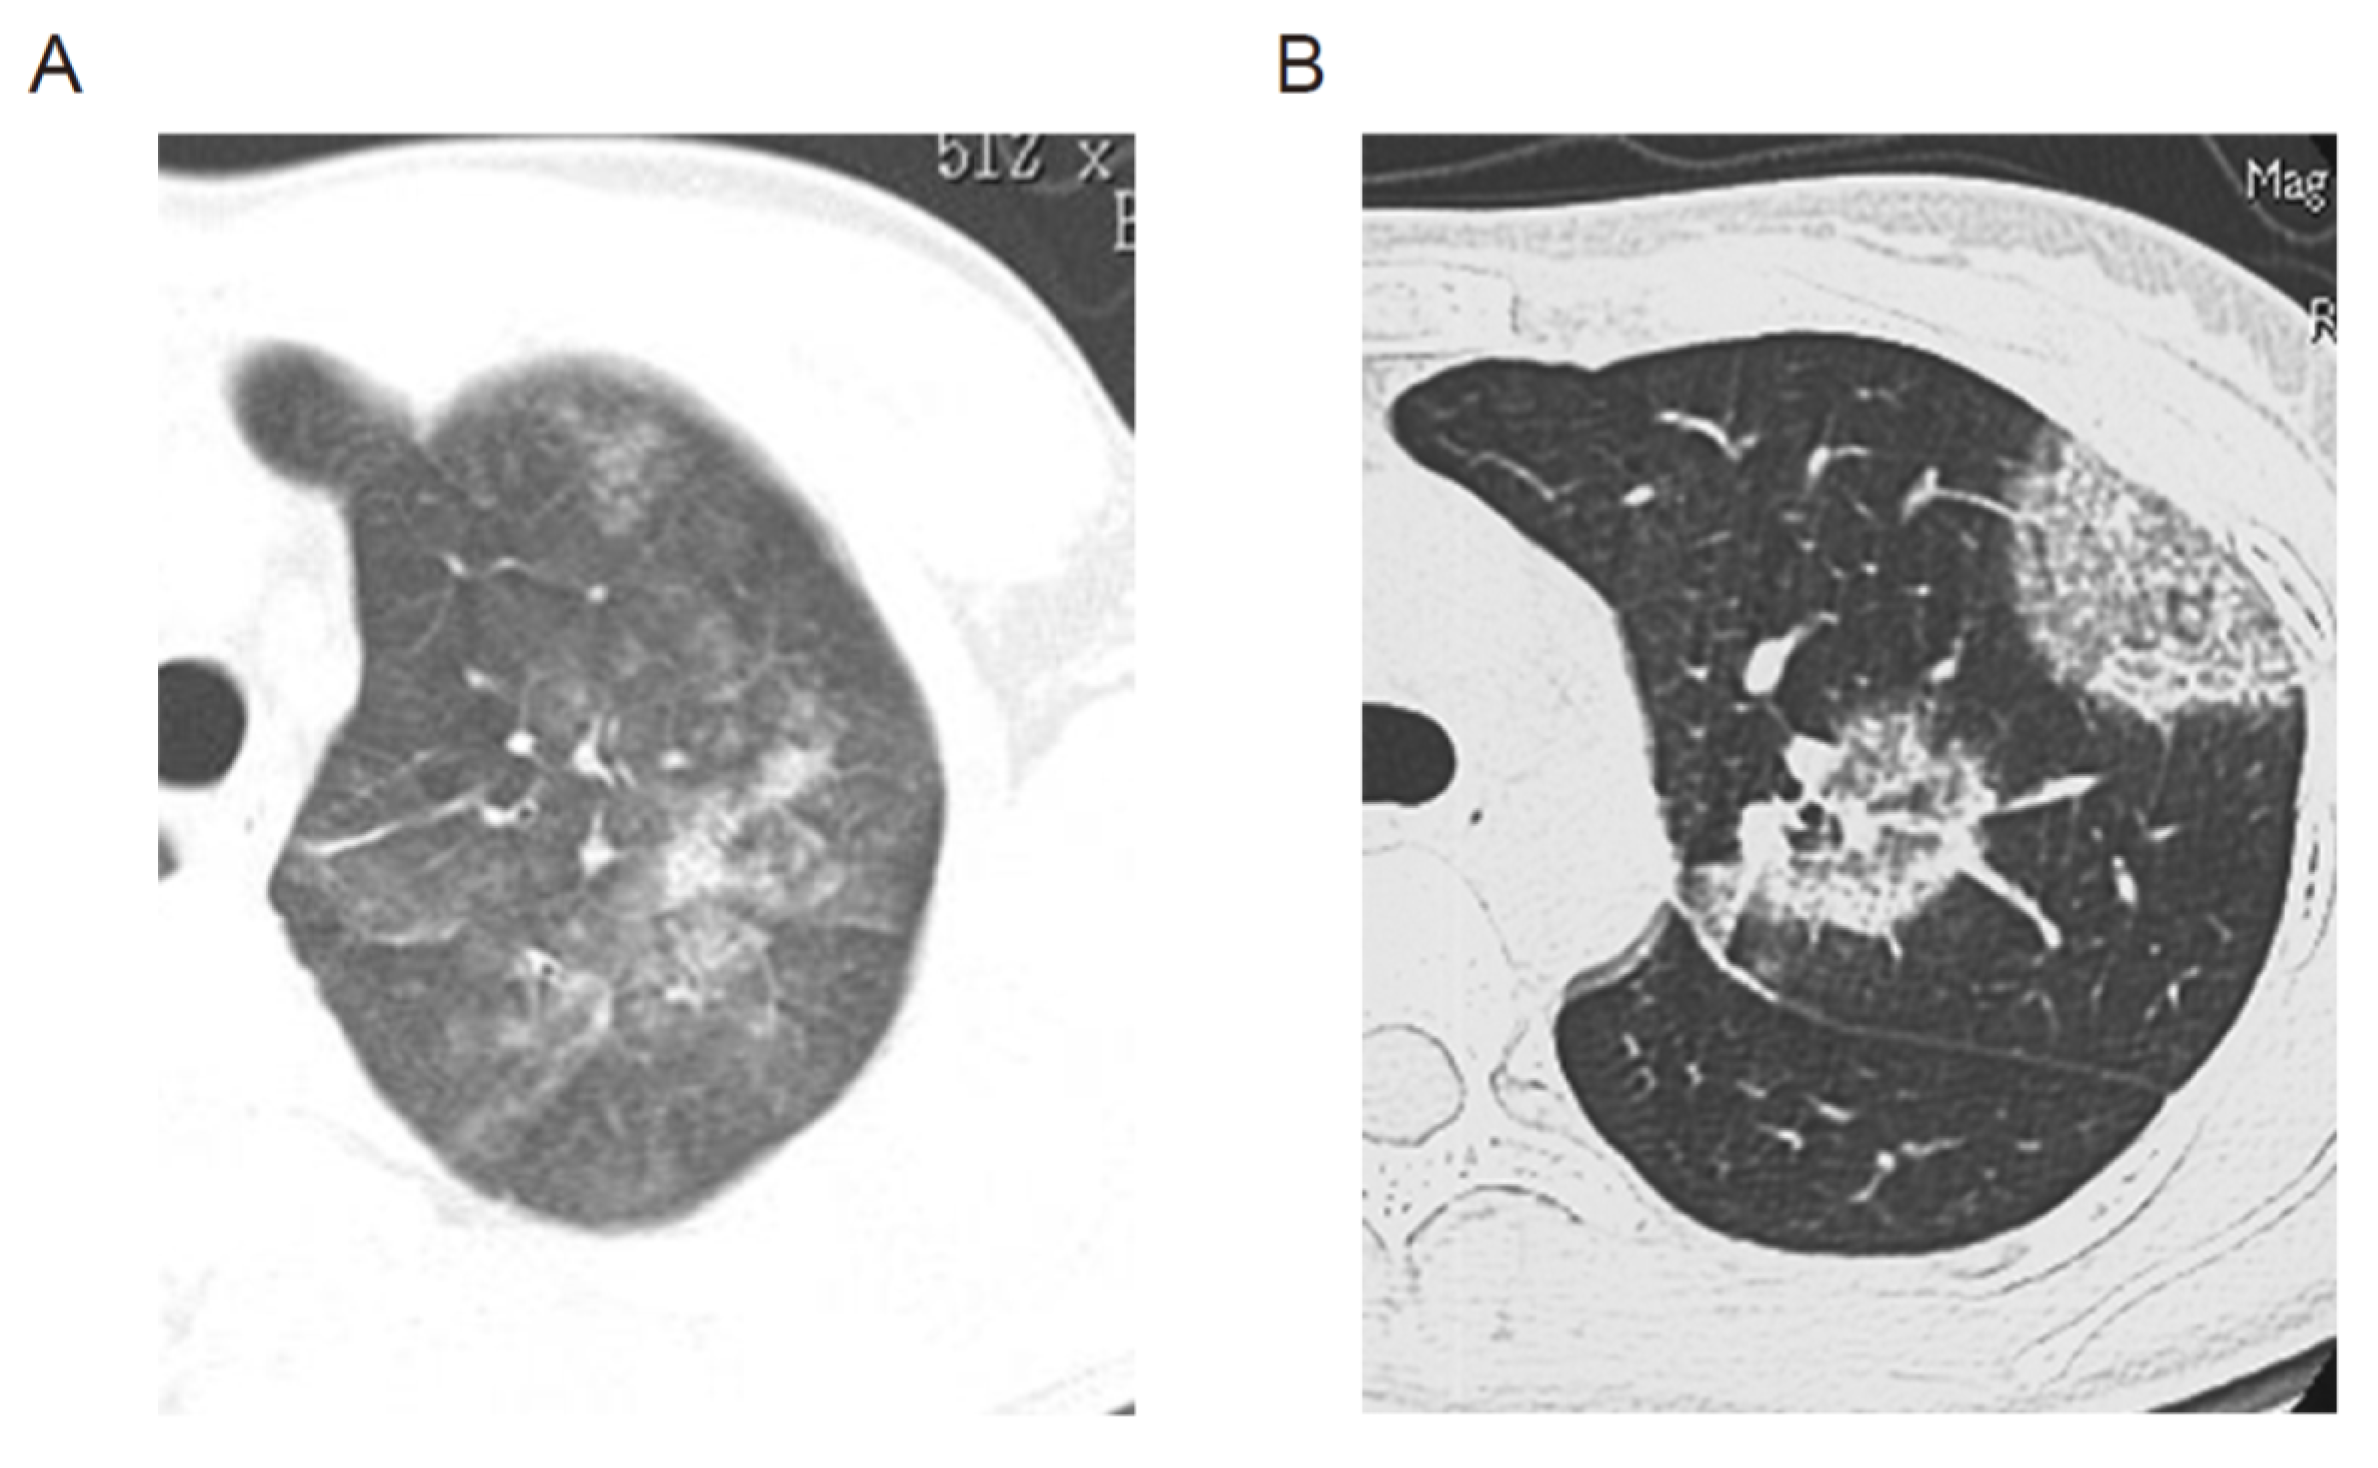

2. AEP and CEP